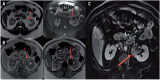

Inflammatory pseudotumor of kidney: a challenging diagnostic entity